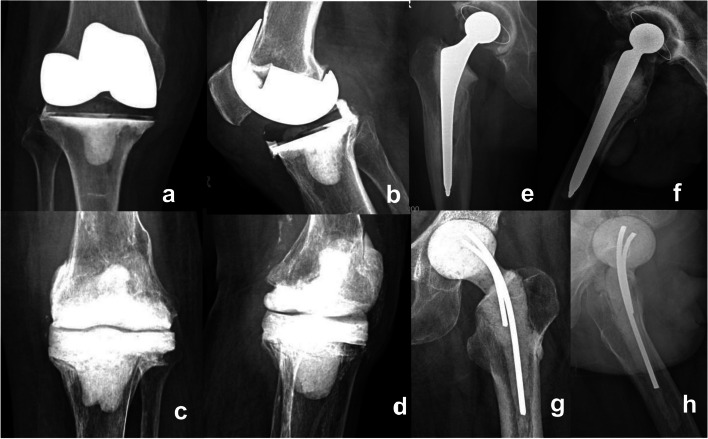

Purpose: The study aimed to compare the infection control rates, mechanical complications, and functional outcomes between prosthetic and cement spacers in two-stage revision arthroplasty for chronic periprosthetic joint infection (PJI).

Patients and methods: Data from patients treated for chronic PJI in our center from 2014 to 2023 were retrospectively collected and the patients were divided into the prosthetic spacer (PS) and cement spacer (CS) groups based on the type of spacer used for the first-stage surgeries. Data on patients' demographics and clinical scores were harvested. Infection control rates and mechanical complications were compared between the two groups by using chi-square tests and log-rank analysis.

Results: The study involved 113 cases, with a mean age of 64 ± 11.45 years (range, 31-88 years), with 48 cases in the PS group, 65 in the CS group, and all patients were followed up for at least 1 year (average 52.68 ± 26.07 months). Five patients in the PS group (10.42%) and six in the CS group (9.23%) developed recurrent infections, with no significant difference found in infection control rates (P = 0.833). The joint function score after the first-stage surgeries was higher in the PS group than in the CS group (P = 0.021). The incidence of mechanical complications, including dislocation, spacer fracture, and periprosthetic fracture, was significantly lower in the PS group than in the CS group (P = 0.024). The proportion of patients who underwent second-stage surgeries was lower in the PS group than in the CS group (58.3% vs 70.77%, P = 0.169).

Conclusion: For most patients with chronic PJI, PS can be used as the preferred option for two-stage revision arthroplasty.